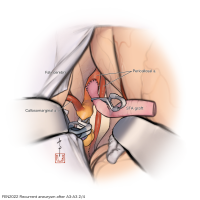

FEN2022シリーズ